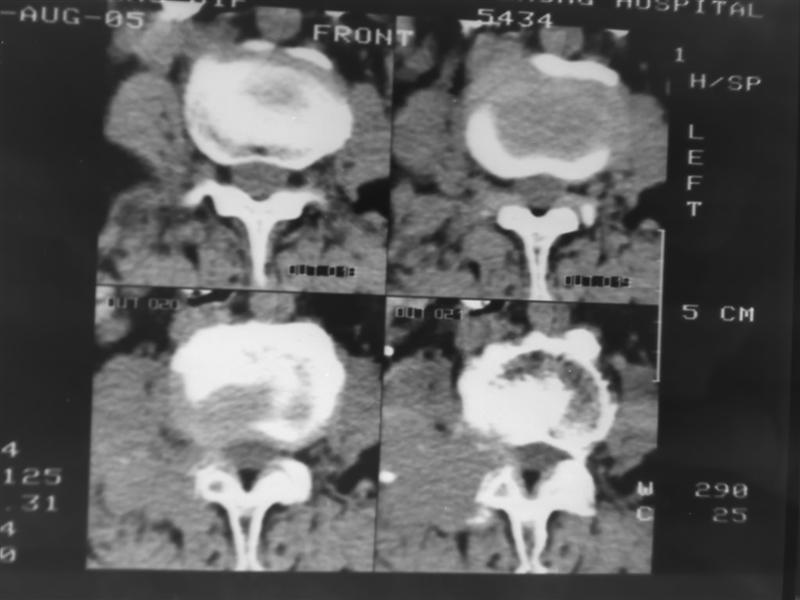

以下是引用老爱克斯新网客在2007-9-27 17:59:00的发言:[br]多个椎体及椎弓跟骨质破坏,并见软组织肿块,符合转移瘤改变,

以下是引用wqs571018在2007-9-27 16:48:00的发言:[br]支持:多发病变,骨质破坏伴软组织块影,符合转移.